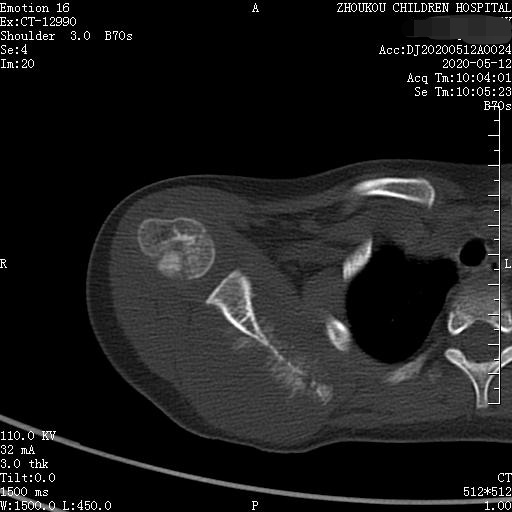

通过CT平扫发现:右侧肩胛骨骨质密度不均,骨质内可见“虫食样”低密度影,骨质边缘可见多发放射状骨针,呈“日光射线征”。周围软组织明显肿胀,肌间隙模糊。CT检查意见:考虑:右肩胛骨占位,骨肉瘤可能,不除外其它恶性肿瘤病变,请结合临床及相关检查注意复查。 影像鉴别诊断:骨肉瘤是指起源于骨间叶组织,遗留形成骨细胞直接形成骨样组织为特征的恶性肿瘤,是比较常见的骨恶性肿瘤,好发于十到二十岁青少年,骨肉瘤常见于管状骨,股骨远端胫骨近端最多见,表现为疼痛局部肿胀运动障碍,实验室检查都有碱性磷酸酶升高。

二、根据骨质破坏和肿瘤骨的多少,骨肉瘤可以分为三型,液化型以肿瘤新生骨为主,溶骨型是以骨质破坏为主,混合型新生骨的形成和骨质破坏并存,x线表现是不规则的骨质破坏伴浸润,可见日光样和放射状骨膜反应,骨膜新生骨在破坏可形成考特曼三角,骨内可见云状、絮状、针状、放射状肿瘤骨伴软组织肿块而形成。